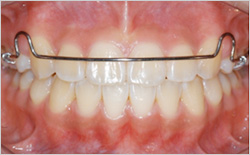

철사와 플라스틱 부분으로 이루어진 유지장치로 환자분이 직접 꼈다 뺐다 할 수 있습니다.

전체적으로 치아를 안정된 위치로 유지해주면서, 위 아래 치아들이 조금 더 자연스럽게 맞아 들어갈 수 있도록 가이드라인 역할을 해줍니다.

가철식 유지장치는 교정치료가 끝나서 장치를 모두 제거한 후, 처음 6개월에서 1년간은 식사 때와 칫솔질을 할 때를 제외하고 하루 종일 장착해야 합니다.

그 후에는 주로 밤시간에만 장착하면서 점차 장착시간을 줄이게 됩니다.